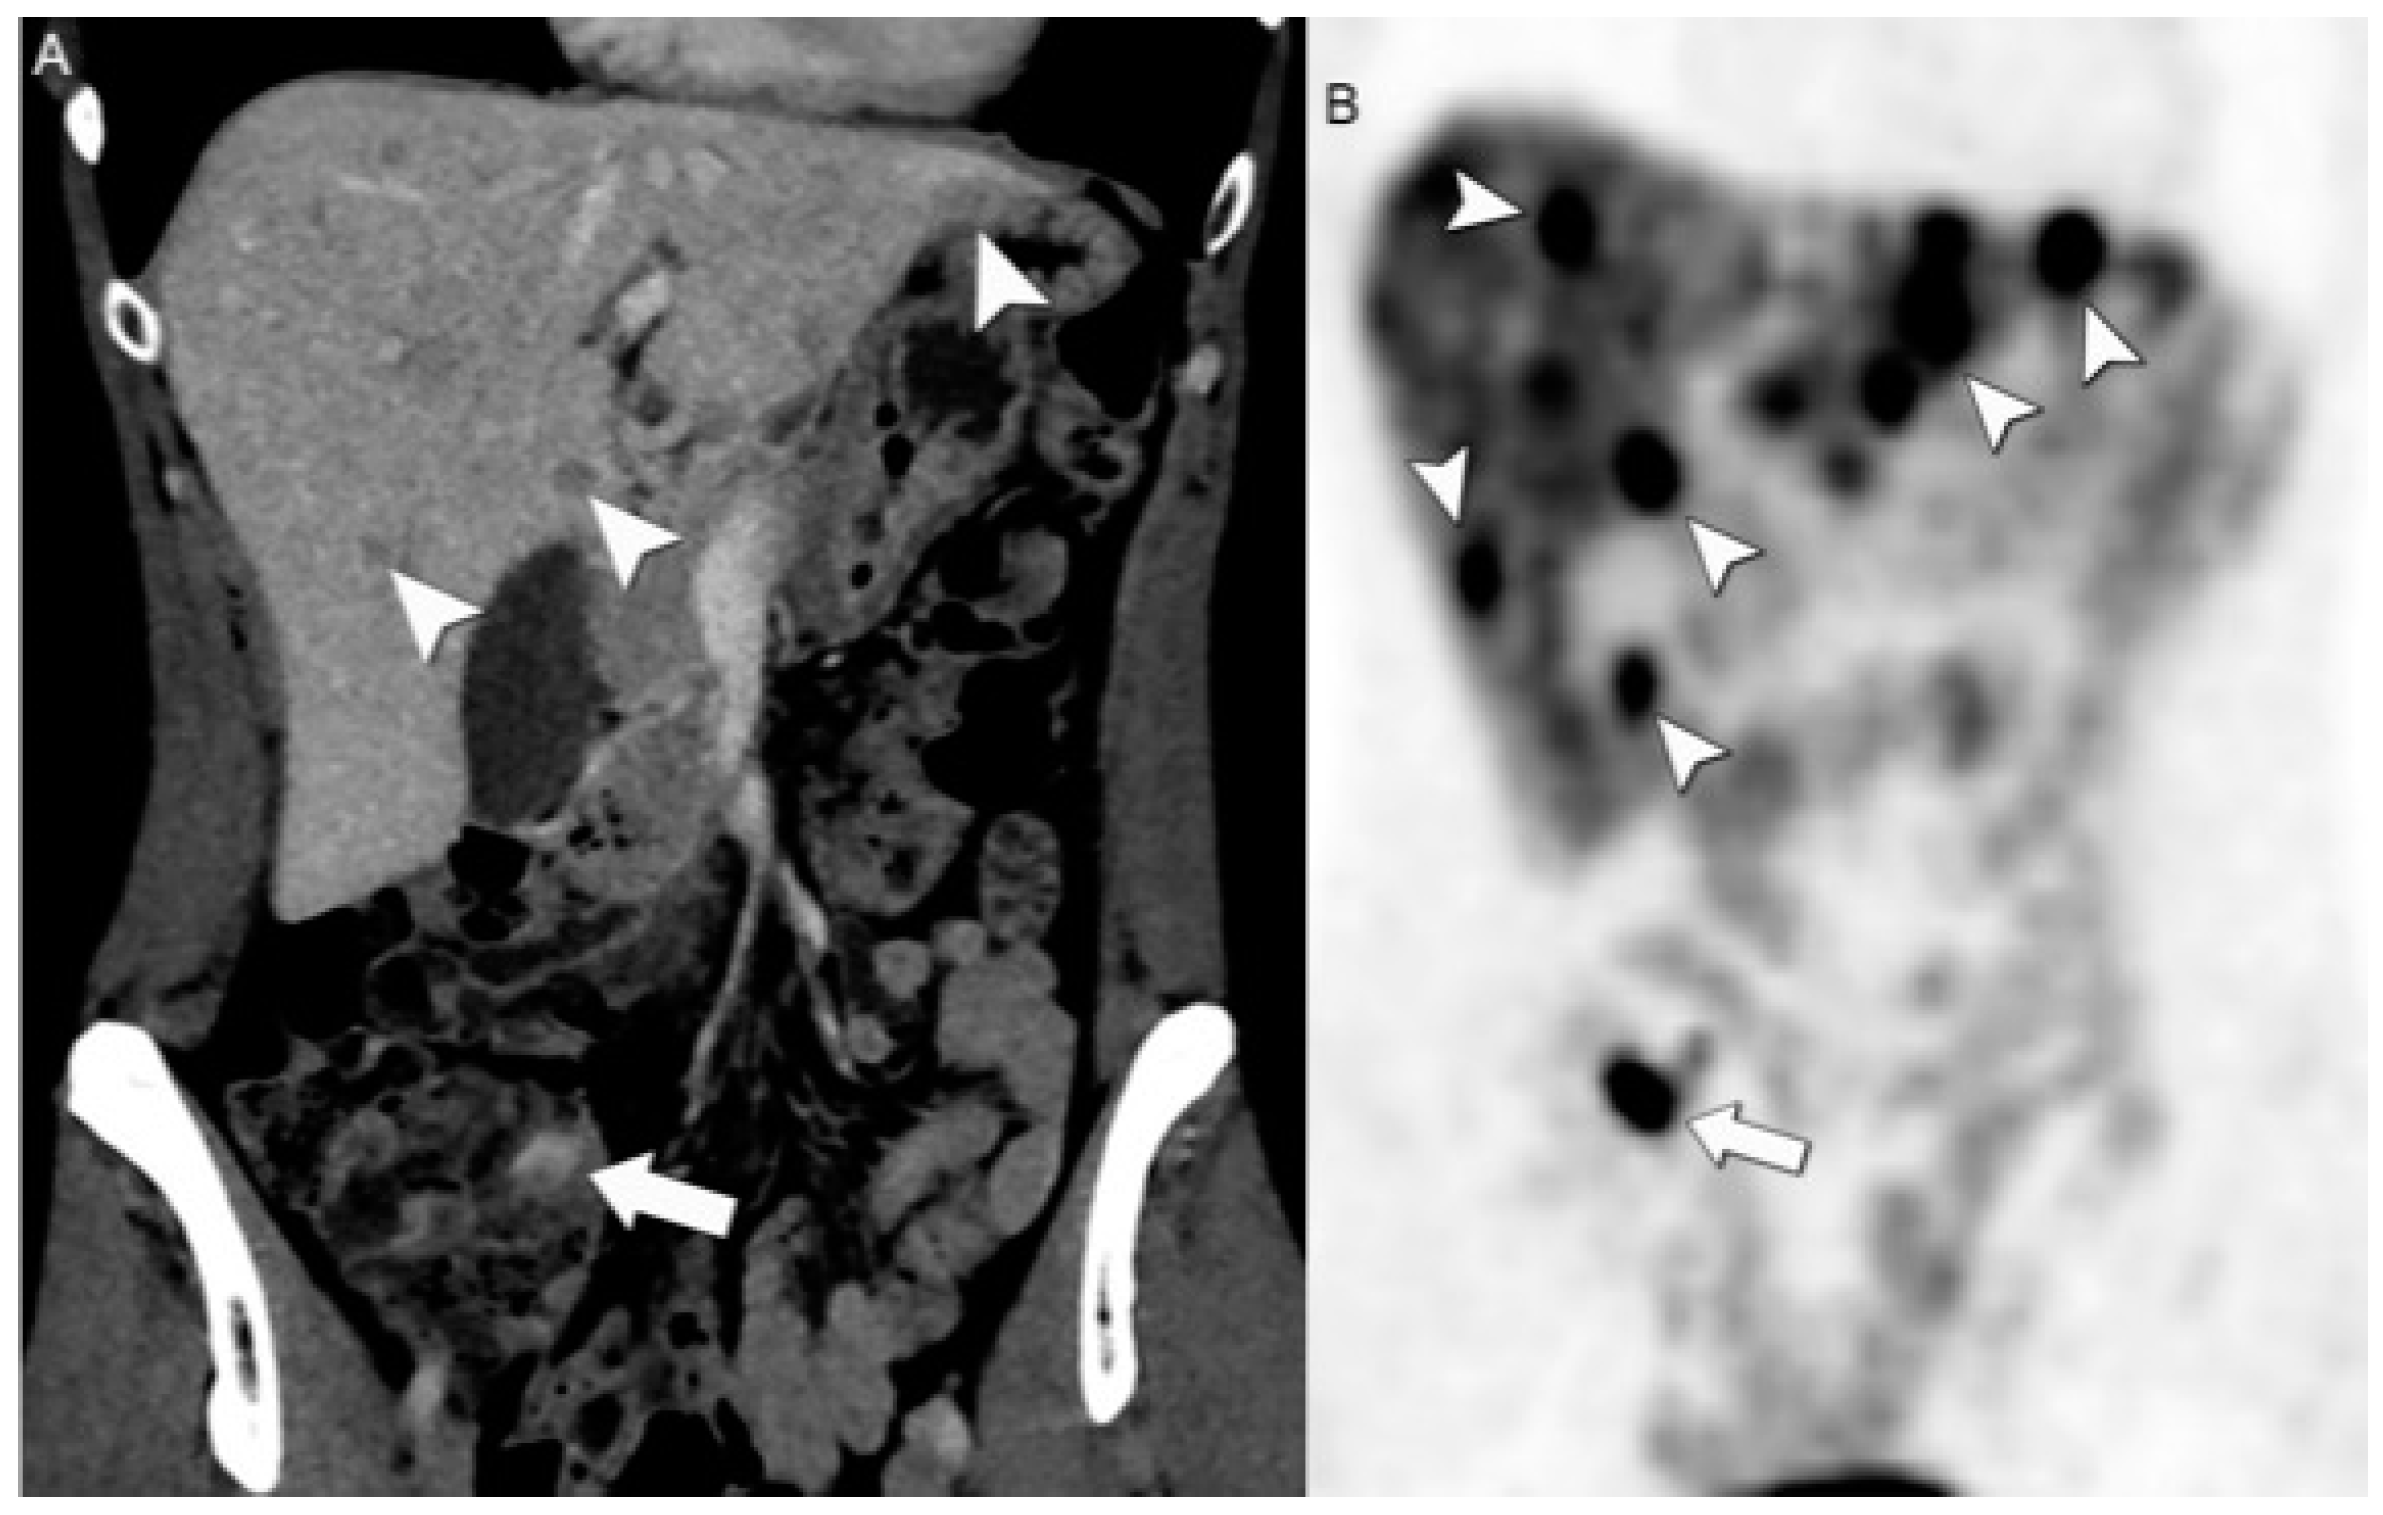

4.2. Hybrid Imaging of NENs